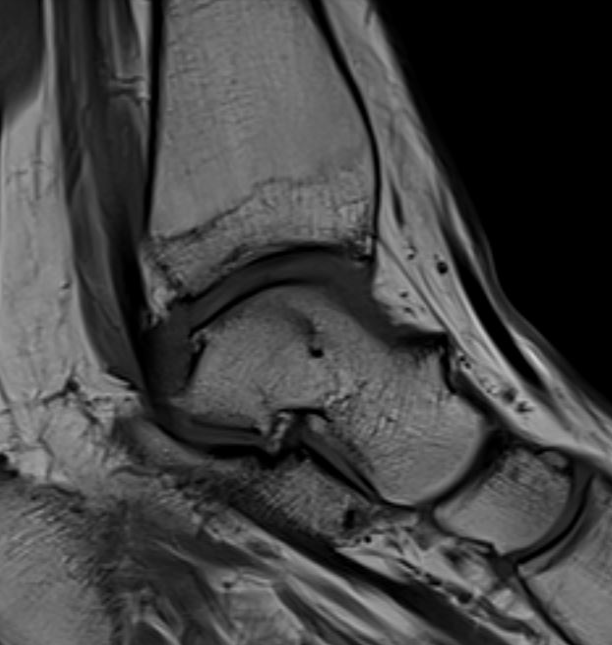

Impingement between anterior distal tibial osteophyte and sulcus of the talus in dorsiflexion

Anterior osteophytes

Soft tissue impingement - scar tissue in anterolateral gutter from recurrent ankle sprains

Anterior tibial and talus spurs with normal joint space

MRI